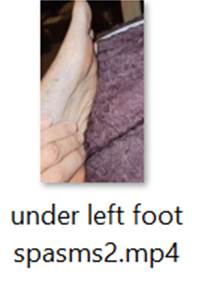

Patient is a 58 year old female physician with past medical history of high cholesterol, celiac disease and multiple food allergies who sustained an open crush fracture of the left big toe in June 2022 after a heavy double glass and metal shower door fell on her toe. She was seen in the ER and received wound care with tetanus booster and trephination of toenail. 2-3 days after injury intermittent twitching was noted in the small muscles surrounding the injured toe. One week after injury, twitching worsened around the medial left foot, progressed to the lateral toes of the left foot, then gradually progressed further up the left leg. Once twitching reached the gluteal muscles (ascending spread), it spread to the all extremities and back. There were several strong tonic contractions of gluteal muscles which lifted the patient off of the couch involuntarily. At this time patient had concern for tetanus and sought initial ID consult. Labs done included Creatinine Kinase which was 602 with normal CBC, CMP and negative blood cultures.

Patient was hospitalized in August 2022 for IV (Intravenous) metronidazole which helped reduce (but not eliminate) symptoms for about one month. MRI of the left toe showed still healing fracture and ortho consult did not recommend surgical intervention at that time. Multiple neurology consults were obtained to rule out neurological cause of symptoms given the unusual presentation and all neurology consults felt this was not primarily a neurological issue and she was referred back to Infectious Disease for management. EMG & MRI of the brain were done and were both normal. (Patient was advised to continue benzodiazepine during initial EMG so any possible exaggerated F-response and spasms were suppressed by benzodiazepines during the EMG). During all physical exams involuntary muscle spasms/ twitching of the left foot/toes were noted involving both agonist and antagonist muscles.

1) Videos of Left Toe & Foot Spasms/Twitching: